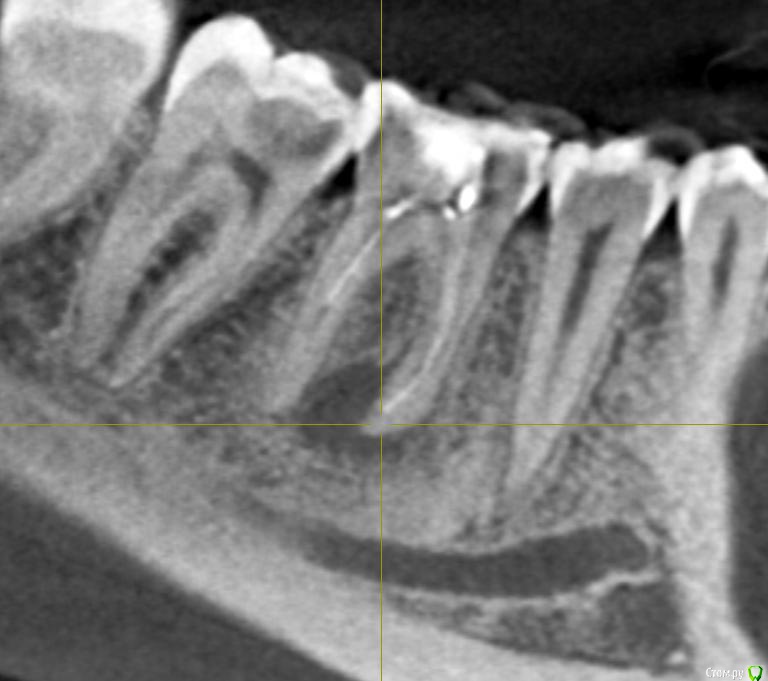

Ксения_ Опубликовано 27 августа, 2015 Поделиться Опубликовано 27 августа, 2015 (изменено) Здравствуйте Уважаемые Доктора! КТ сделано 4 мес назад. После этого пролечен кариес 14, 16, 37, 35. Пролечен пульпит 25, 36.Осталось пролечить пульпит в 15, 26, 47. Удалить все восьмерки.Далее ортодонтия. Стоит вопрос об удалении 46. Зуб ранее был пролечен другим врачом некачественно (+ пропущен канал).Мой лечащий доктор, после консультаций с коллегами, предлагает удаление, т.к. с его слов прогноз у этого зуба неблагоприятный (считает, что через пару лет процесс повторится) и смысла в столь дорогом лечении нет. Мне, конечно, хотелось бы по возможности зуб сохранить.Как вы считаете какой прогноз у этого зуба? P.S. Зуб не беспокоит. Точнее ни один зуб у меня вообще ни разу в жизни не болел (несмотря на такое количество пульпитов, которые для меня были неожиданностью. Врачу своему доверяю.). Несколько докторов которые меня смотрели считают, что у меня высокий болевой порог. Изменено 27 августа, 2015 пользователем Ксения_ Ссылка на комментарий

M@estro Опубликовано 27 августа, 2015 Поделиться Опубликовано 27 августа, 2015 (изменено) Судя по рентгену - прогноз благоприятный. Зуб сохранен,это главное. "процесс повторится" - на это при современном подходе выделяют не более 5 % .Если бы у меня 95 % вероятности в казино было - я бы дом поставил , не то что зуб полечил ) Ключевое при перелечивании - соблюдение современного протокола лечения. P.s. После лечения уже больше двух лет прошло,недавно был на осмотре - процесс все никак не повторится )) Изменено 27 августа, 2015 пользователем M@estro 3 Ссылка на комментарий